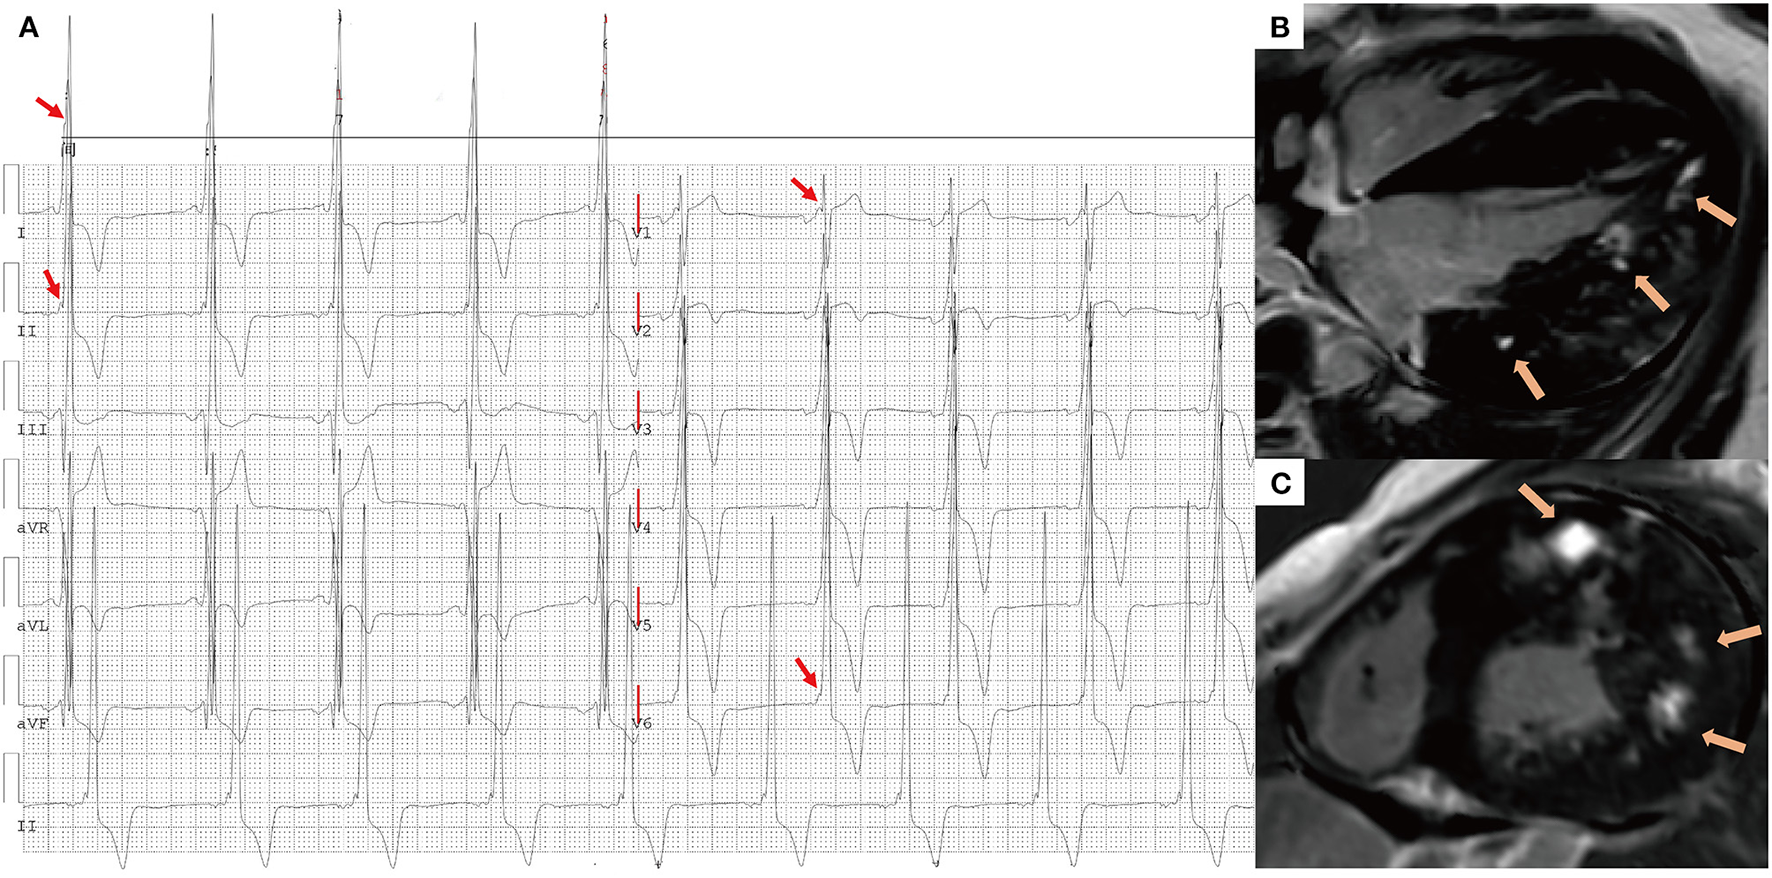

A 16-year-old male presented with chest tightness and shortness of breath and was genetically diagnosed with Danon disease (mutation site: c.936G > A). (A) f-QRS with a notched R pattern (red arrows) were found in the lateral leads (I, aVL, V6); the total f-QRS score was 3. (B) Four-chamber view and (C) short-axis view of LGE images on CMR showed patchy fibrosis/scarring in the lateral wall of LV (orange arrows). Global LV LGE% was 20%. f-QRS, fragmented QRS; LGE, late gadolinium enhancement.

Figure 5

A 17-year-old male presented with chest tightness, shortness of breath, and syncope and was genetically diagnosed with Danon disease (mutation site: c.35C > A). (A) f-QRS was found in 12 leads. Notched R/S patterns (single red arrows) were found in the I, II, aVL, and V1–V6 leads. The fragmented QRS pattern was found in III and aVF leads (double red arrows), and the total f-QRS score was 15. (B) Four-chamber view and (C) short-axis view of LGE images on CMR showed the extensive fibrosis/scarring in the lateral wall of LV and patchy fibrosis in the septum (orange arrows). Global LV LGE% was 36.7%. LGE, late gadolinium enhancement.